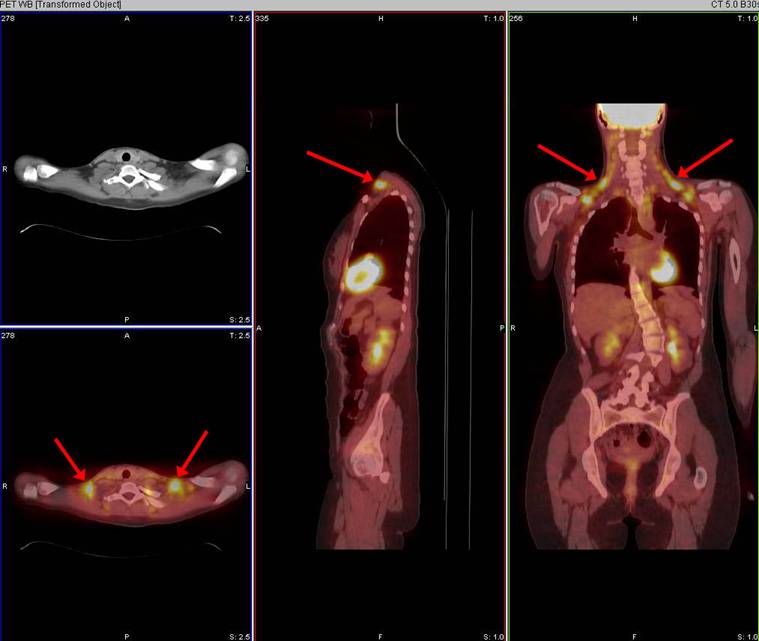

Often a pattern of multi-focal intense symmetric uptake along the neck, supraclavicular regions, mediastinum, and paraspinal regions can be seen, especially in children. The PET/CT fusion images localize this uptake to areas of fat, rather than to any other soft tissues.

22-year-old female patient with history of large B-cell lymphoma status post 6 cycles of chemotherapy. PET/CT ordered for restaging. Symmetrical FDG activity is seen within brown fat in the neck and chest, a benign finding.